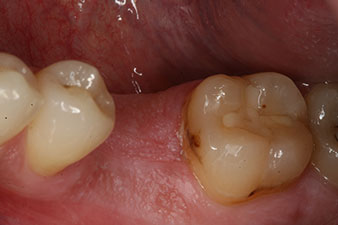

measuring probe

Fig. 6: Ten weeks later the gingiva former, which was screwed in place after placement of the implant, can be removed. In the linguo-buccal direction the ISQ value was virtually unchanged at 63 (measuring probe in proximity at a distance of 2-3 mm).

These values could have indicated open healing or even immediate restoration. Due to the insufficient crestal bone volume at the implant, the region was augmented with the bone chips collected during preparation of the implant bed and sutured to exclude saliva.

The implant was uncovered two months later and a gingiva former was screwed in (no picture).